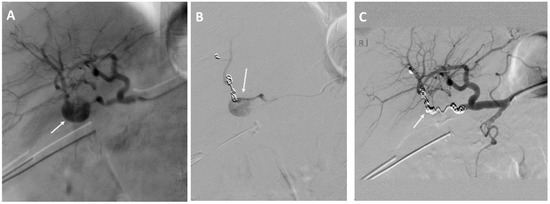

Figure 2.

A 73-year-old woman with a history of intraductal papillary mucinous cancer of the pancreatic head and pylorus preserving pancreatoduodectomy (PPPD). (A,B) Angiography showing bleeding from the superior mesenteric artery. (C) Treatment of the superior mesenteric artery with a stent-graft.

Coiling of the eroded vessels was done in 28 (78%) of the EVT patients and in three (10%) of the OS patients who developed recurrent bleeding. The median number of coils used was seven coils (range, 2–23 coils) see Figure 3.

Figure 3.

A 74-year-old man with a history of cholangiocarcinoma of the extrahepatic bile ducts treated with resection of the bile ducts and biliodigestive anastomosis. (A) Angiography showing bleeding from the right hepatic artery. (B,C) Endovascular coil embolization of the right hepatic artery.